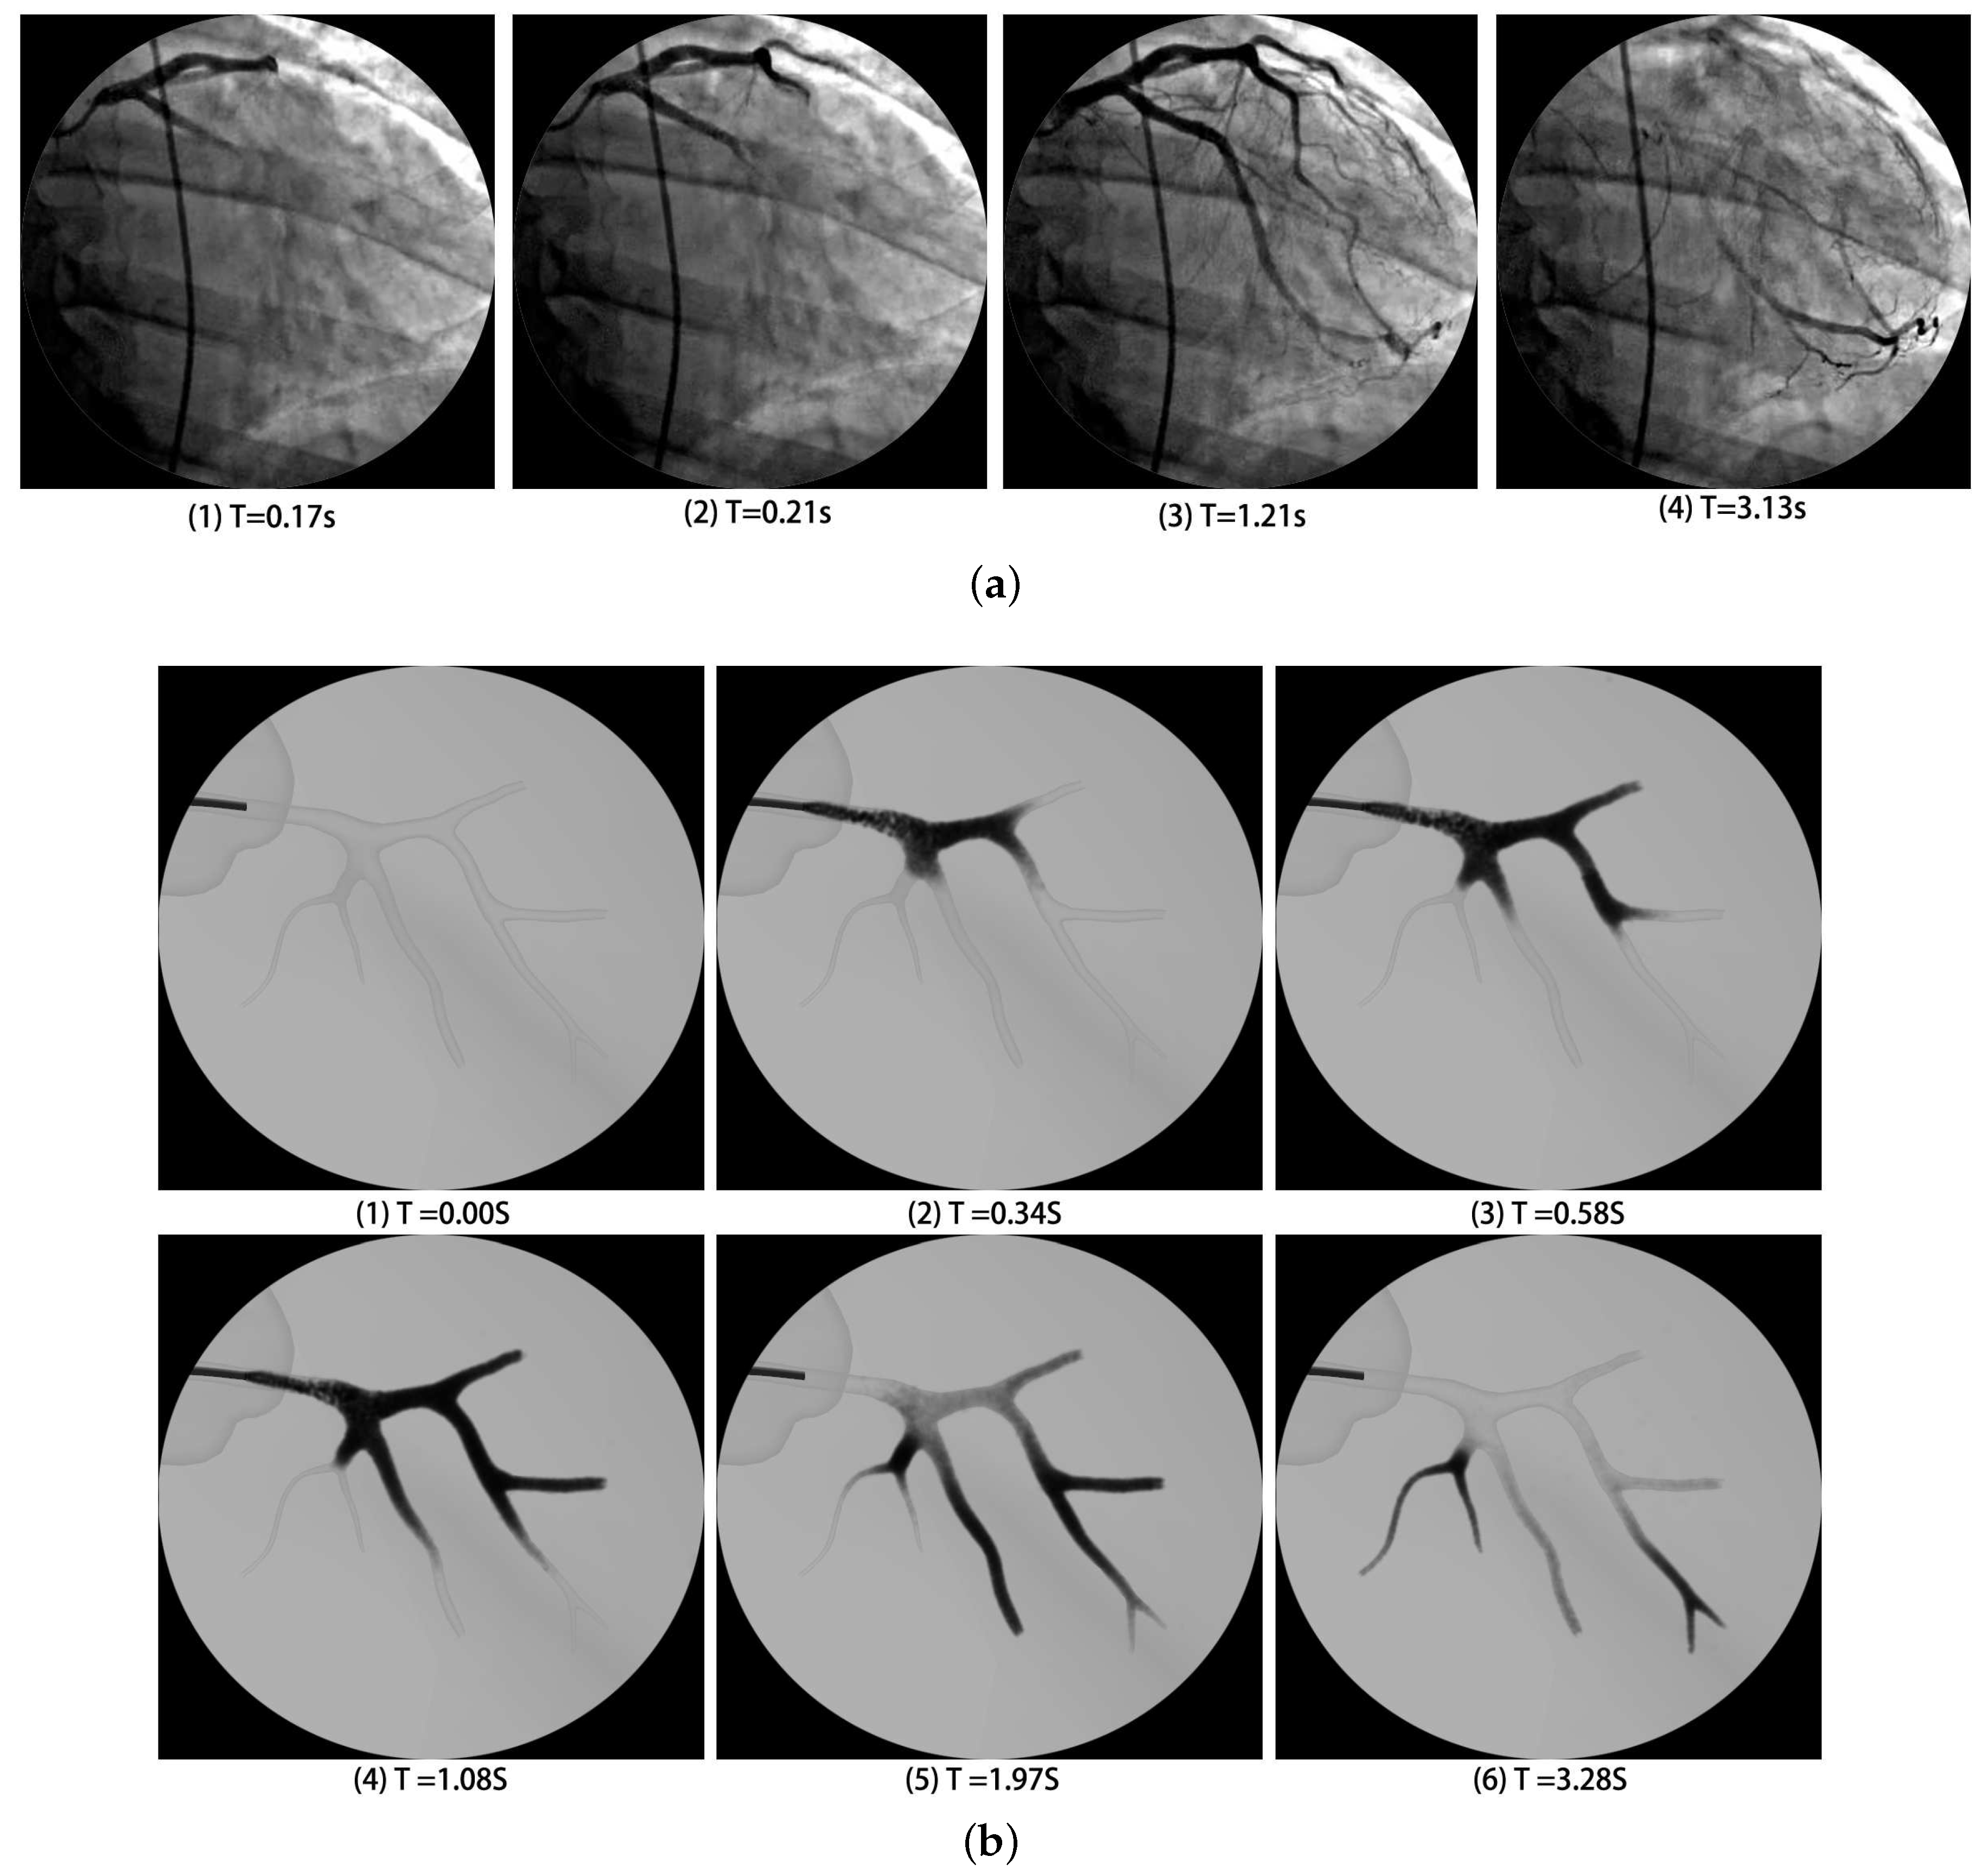

4.2.3. Virtual and Real Angiography Results Comparison